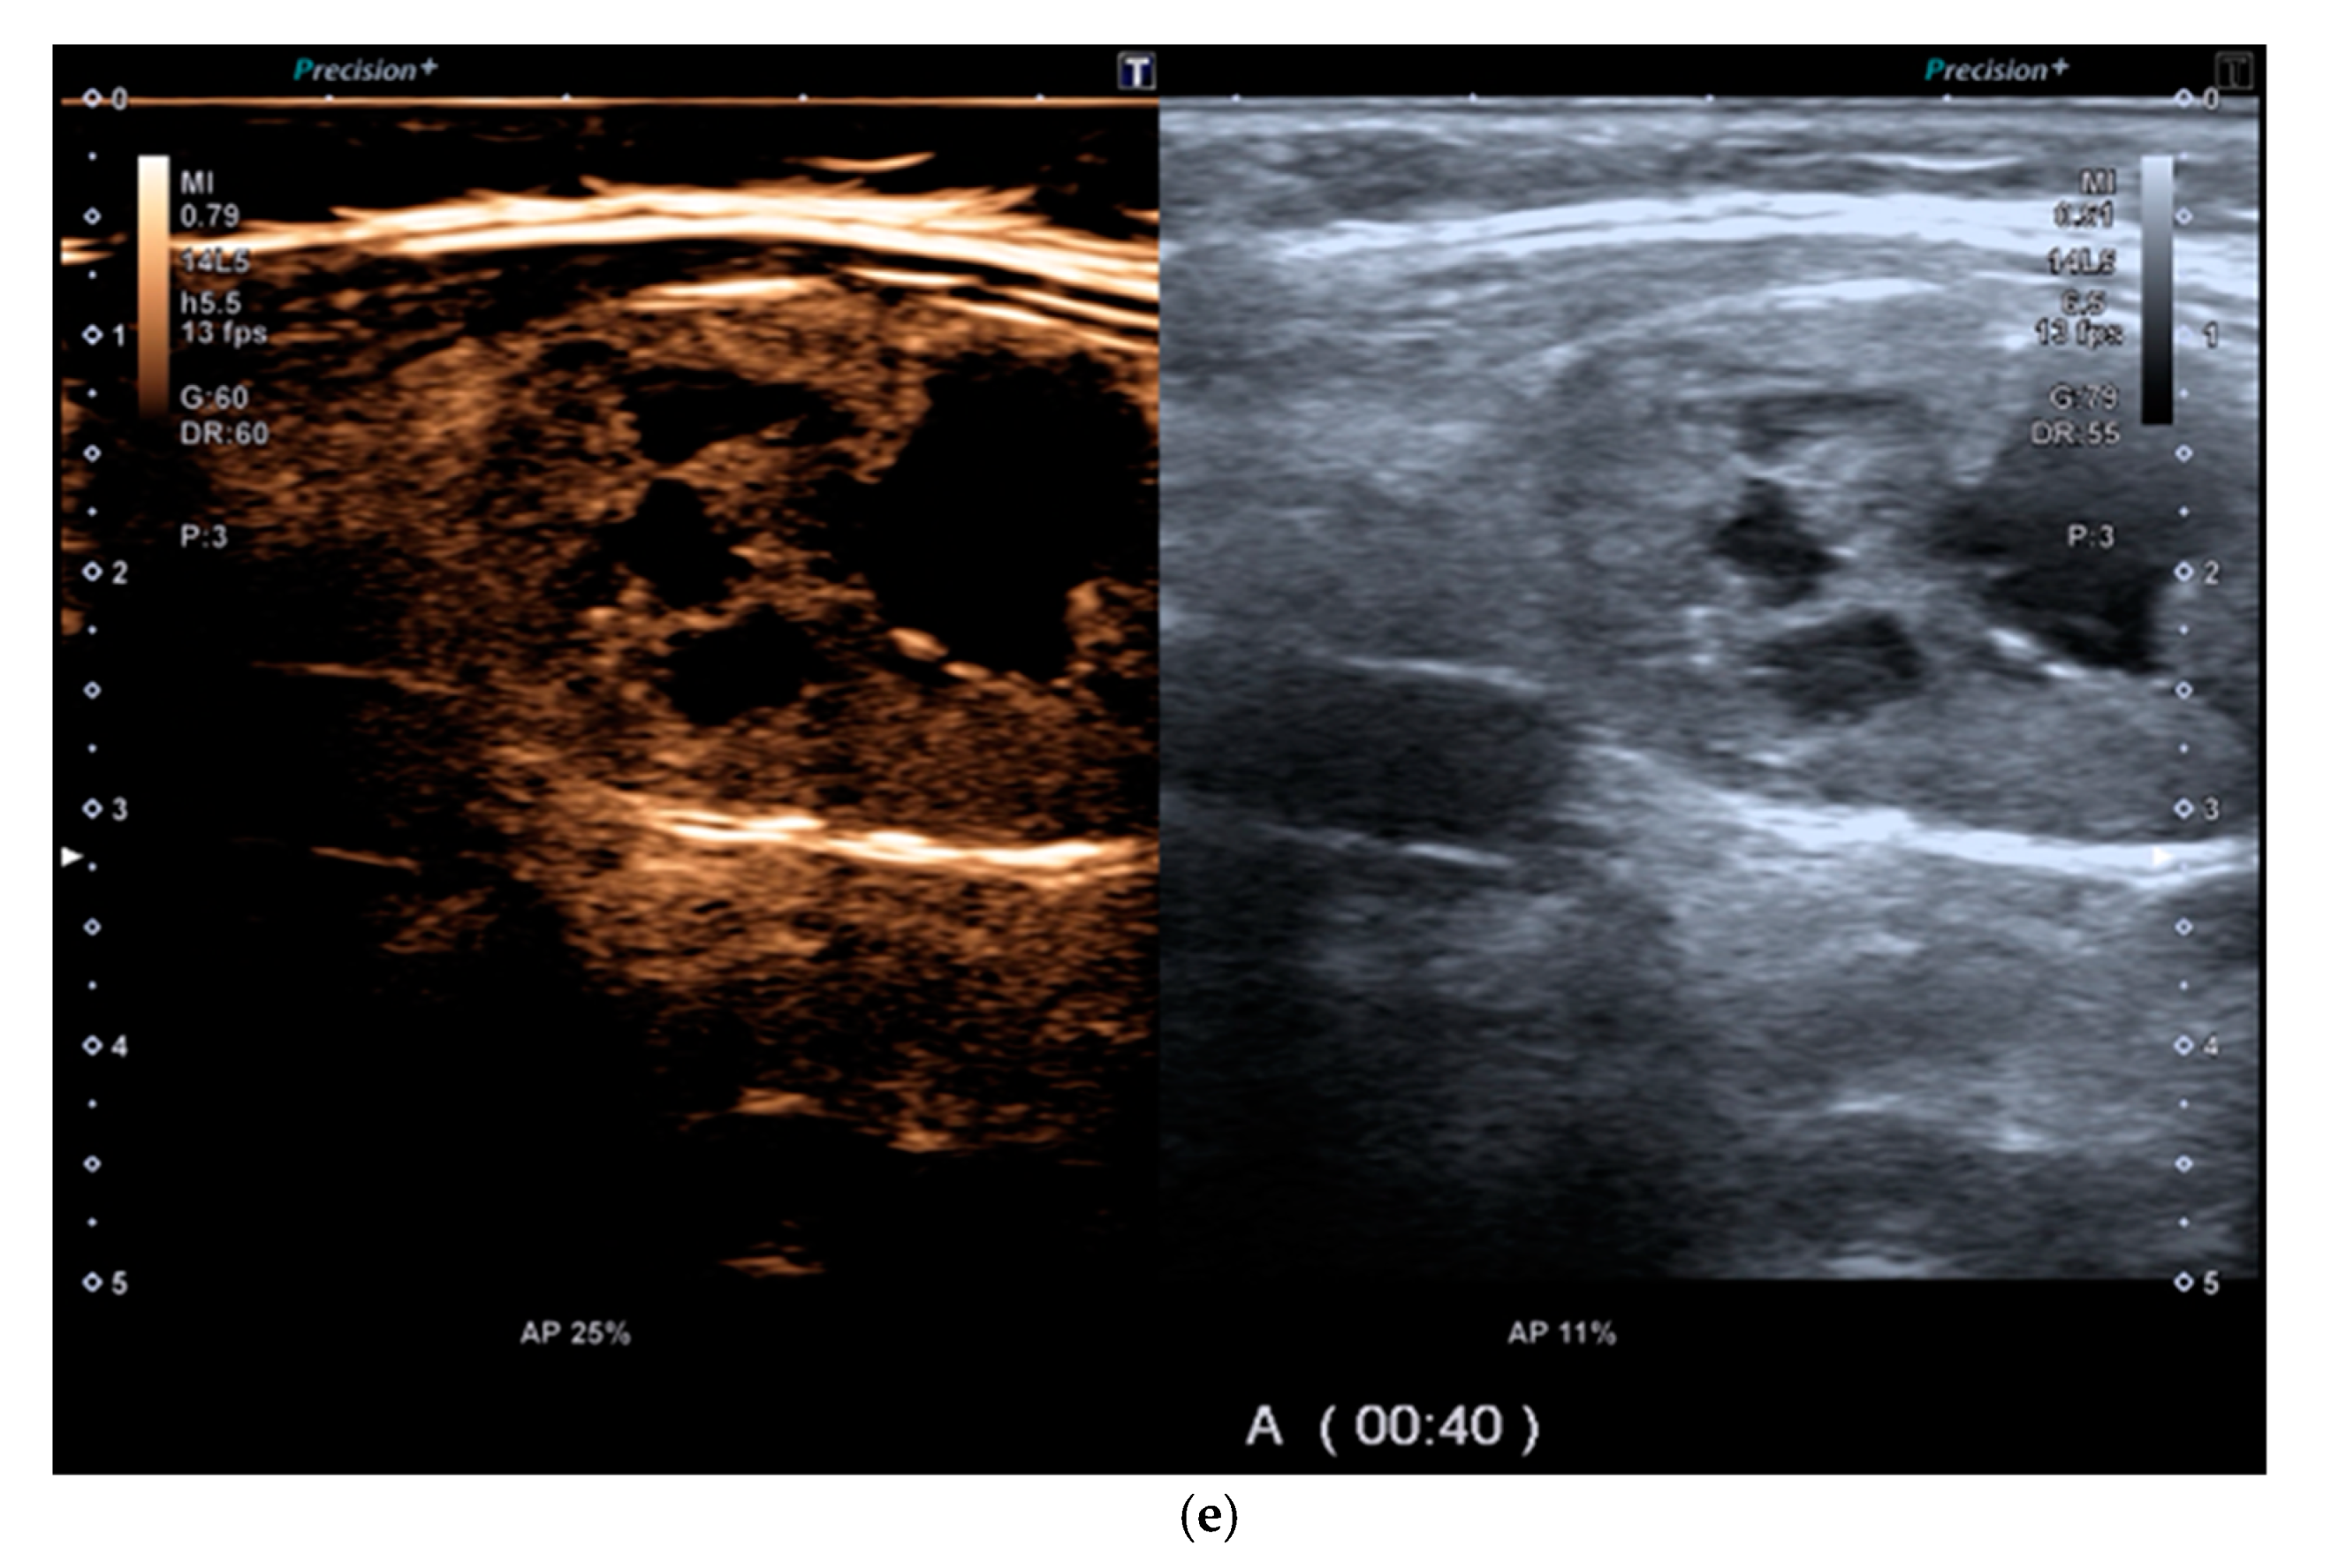

6. Multiparametric Ultrasound

Multiparametric Ultrasound (MPUS) Role for Indeterminate Thyroid Nodule Evaluation